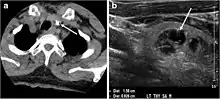

Fig. 4. A 45-year-old male patient presented with anterior mediastinal metastatic PTC lesions and occult primary on imaging. Histopathology examination of the resected thyroid gland revealed micro-foci of PTC; the largest, in the isthmus, measured 4 mm. a transverse greyscale ultrasound of the thyroid demonstrates homogeneous gland with normal echogenicity and size. No focal lesion or micro-calcifications. b Non-enhanced CT scan obtained as part of PET/CT examination shows a heterogeneous, large, relatively dense anterior mediastinal mass (white arrow) with peripheral calcification (arrowheads). Thyroid gland has normal CT appearance with no abnormal FDG uptake (not shown).[1]